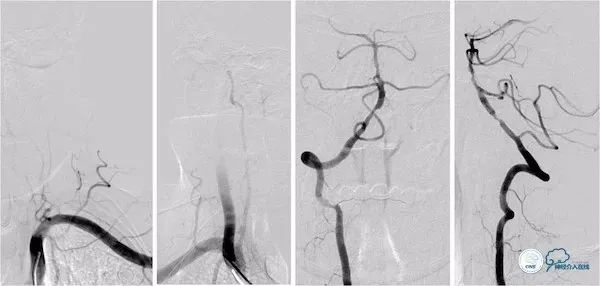

治疗过程简述:全麻下右股动脉入路, 6F Guiding导引导管至右椎动脉V2段远端,术中造影示右椎动脉V4段重度狭窄,基底动脉中段中重度狭窄(图11)。

图11

将Transend微导丝(0.014″,300cm)通过狭窄,放置在左小脑上动脉,沿微导丝送入Gateway球囊(2.0mm×15.0mm)于狭窄处预扩张(图12)。

图12

撤出球囊导管,沿Transend微导丝送入Wingspan自膨式支架(3.0 mm×20.0mm),释放后造影示支架贴壁良好,前向血流TICI 3级(图13,14)。

图13

图14